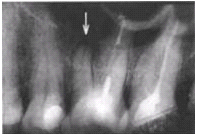

Дифференциальный диагноз свищевого хода. Если свищевой ход

открывается в десневую бороздку или по передней складке, источник инфекции

определяется путем введения гуттаперчевого штифта. Его преимущество заключается

в гибкости и инертности.